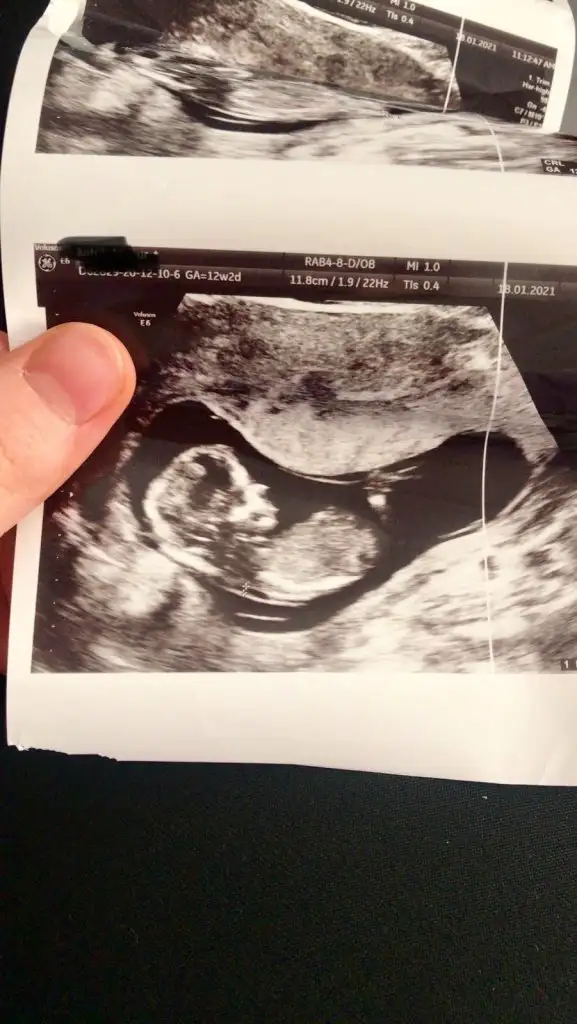

Erkek görünüyorAmin canım hepimizin12 haftalık usg resmi benimde

Bakalım bu hafta gidicem büyük ihtimal söyler heraldeErkek görünüyor

Erkek görünüyorMerhaba 11+6 tahmin edermisiniz

Net değil nubu emin olamadim başka USG varsa paylaşın sanki kız ama emin değilimMerhaba 12 haftalık tahmin edebilir misiniz![]()